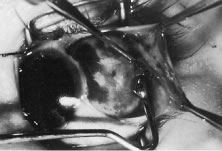

RECESSION PROCEDURE: LIMBAL APPROACH

Two 6-0 silk stay sutures are passed through the conjunctiva and superficial scleral tissue at the limbus (see Fig. 49). These sutures are used to stabilize the globe during the procedure. These stabilizing sutures attached to bulldog clamps will hold the globe in adduction or abduction as required.

A no. 15 surgical knife or other similar instrument is used to penetrate the conjunctiva at the limbus (Fig. 50). Care is taken to approach the limbustangential to the globe so that inadvertent penetration of the sclera or cornea is avoided. A Westcott scissors also may be used to incise the conjunctiva at the limbus. To facilitate this step, conjunctiva is lifted gently with a 0.5-mm Castroviejo forceps (see Fig. 50).

|

A blunt-tipped Westcott scissors is used to extend the incision for about 3 clock hours (Fig. 51). Once the fused area of conjunctiva and anterior Tenon's capsule has been penetrated, blunt dissection is performed to carry the limbal incision back toward the muscle. This maneuver is best accomplished by directing the closed tips of a blunt-tipped Westcott scissors into the tissue and letting them open to spread the tissue in a plane between the scleral surface and the underside of Tenon's tissue. The limbal incision is extended radially with a Westcott scissors (Fig. 52). Care is taken to avoid cutting into the anterior portion of the rectus muscle insertion (Fig. 53).

|

|

Figure 54 shows the conjunctiva being elevated by the assistant with Castroviejo forceps. The anterior extension of the muscle can be seen.

|

A Jameson hook is passed under the rectus muscle about 2 mm posterior to the insertion (Fig. 55). The insertion has been identified previously with a Stevens' hook that is used to lift up the tendon to facilitate passage of the Jameson hook.

Figure 56 shows sharp dissection of the intermuscular septa and the check ligaments that extend from the orbital surface of the muscle. The assistant applies gentle traction to the conjunctiva to show the surgeon the weblike bands that are to be cut. Care is taken not to penetrate the muscle capsule because penetration can injure the muscle and will cause bleeding. This dissection is carried back about 4 to 5 mm for recessions and 5 to 9 mm for resections.

A single-armed 6-0 synthetic absorbable suture is passed through the muscle tendon near its insertion (Fig. 57). A double-lock bite is taken with the needle, and the suture is tied with two square knots to secure it to the upper and lower poles of the tendon of the rectus muscle. The muscle is lifted or tented off of the surface of the globe with a Jameson hook. A Westcott scissors is used to cut the muscle free (Fig. 58).